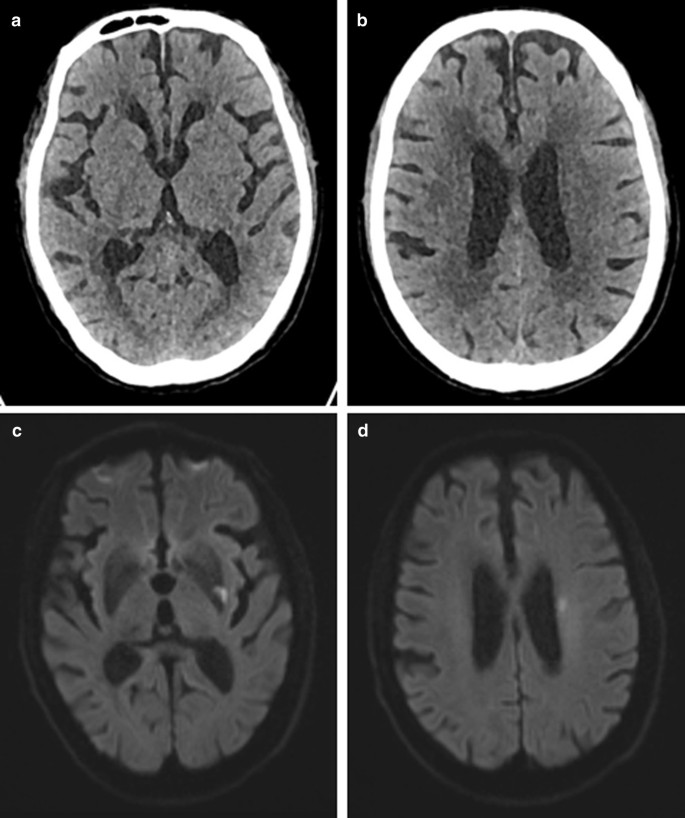

The ASPECTS is a scoring system for evaluating early ischemic changes in the blood supply area of the middle cerebral artery by NCCT. It is essentially based on visually low attenuation. In addition, the ASPECTS is time-dependent, and a study shown that the reliability of ASPECTS is moderate at stroke onset time < 90 min, good at 90–180 min, and excellent at > 180 min. The HU value is based on the attenuation coefficient of water to calculate the HU value of each tissue [17], which is quantitative in nature, and the measurement of HU value is independent of the subjective interpretation of any observer. Compared with the ASPECTS, the reliability and consistency of the HU value are greatly improved. In this study, two patients had the same ASPECTS, but their HU values changed differently, and their clinical outcomes were different (see Figs. 4, 5). The ROC curve showed that the AUC of the HU ratio was 0.743, when the cutoff value was 10, it had a higher sensitivity of 80.56%. The AUC of the HU difference was 0.833, when the cutoff value was 13.97, it had a higher specificity of 93.75%. The results indicated that the HU ratio and HU difference had important predictive value for the prognosis of stroke patients treated by IVT. For stroke patients with the same ASPECTS, the HU value can be used for a second evaluation to improve the accuracy of diagnosis. In the future, more research is needed to perfect this algorithm to improve the predictive value of HU. Our study has some limitations: ① The influence from the occlusion position on the patient was not taken into account, for stroke patients with a distant occlusion position, the infarct size was too small, and the HU value did not change significantly. ② Previous study shown that the weight of each area of ASPECTS was different [18]. We did not weight each area when calculated the HU ratio or HU difference. ③ The sample size was small. ④ No subgroup analysis based on ASPECTS. ⑤ Ten ASPECTS regions were manually outlined and maybe there is an deviation. ⑥ The HU difference or ratio per patient without error used subsequent research and analysis may cause statistical error. In the future, we will adopt imageomics or deep learning methods to avoid it.

Patients with good clinical prognosis: a patient was admitted to the hospital 30 min after the onset of stroke. At admission, the patient's ASPECTS was 9 points, and the HU difference was 12.94. The infarct volume calculated on the DWI image at 7 days after thrombolysis was 4.14, and the 3-month mRS score was 2 points. a, b NCCT image on admission. c, d DWI image at 7 days after thrombolysis

Patients with poor clinical prognosis: a patient was admitted to the hospital 277 min after the onset of stroke. At admission, the patient's ASPECTS was 9 points, and the HU difference was 16.01. The calculated on the DWI image at 7 days after thrombolysis was 231.95, and the 3-month mRS score was 4 points. a, b NCCT image on admission. c, d DWI image at 7 days after thrombolysis